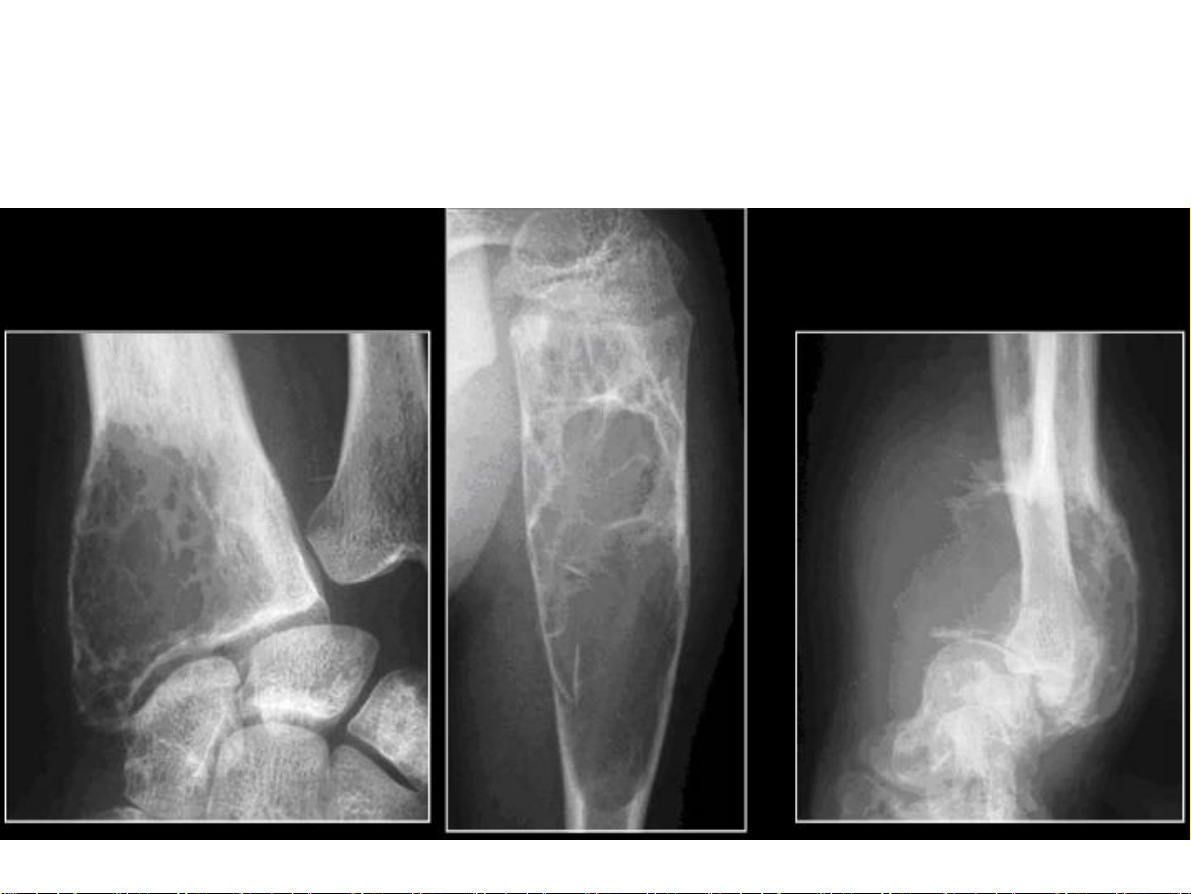

Hai ví dụ của quá trình tân tạo xương. Phản ứng đặc xương ở chỏm

xương đùi và mái ổ cối trong thoái hóa khớp háng (hình A). Đặc xương

lan toả ở cột sống thắt lưng, xương cùng và xương chậu hai bên trong di

căn xương từ ung thư tiền liệt tuyến (hình B). 31-Jan-23 CĐHA Cơ-Xương-Khớp